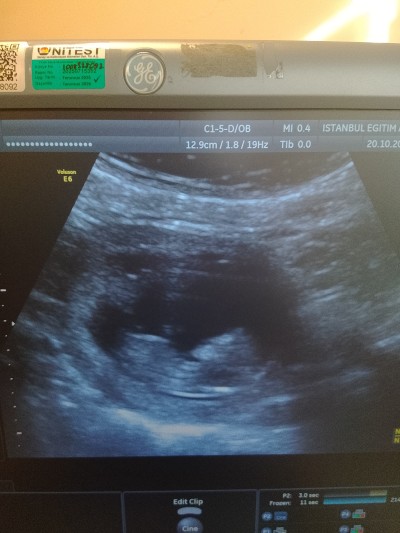

Kizlar cinsiyet için daha erken ama ben yinede merak ettim ama bı tahminde bulunabilir misiniz :) tabiki öncelik sağlıklı olması kız erkek farketmez ama insan yinede merak ediyor 11+4 haftalık

Ultrason fotoğrafını benimkine benzettim cinsiyetimiz kız. Hayırlı sağlıklı olsun

Kız canım yüz şêkli anımsattı cene yapısı kız çocukların sivri olur derler hayirlisi

Nub çıkıntısı bize gösteriyor ki bu bir kız 🥰

Kıza benzttim